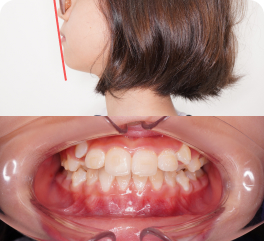

• The child developed a turtle neck posture to open up the airway.

See the improvement in neck posture after the airway is opened up with lower jaw advancement.

Before

(Turtle neck)

After

(Good, upright posture)

Yes, when your child adopts “bad posture” in order to breathe.

Airway issues such as restricted airway from under-developed jawbone, mouth breathing, or improper jaw development may cause a child to tilt their head forward to breathe more easily, which will affect neck posture over time.

Early treatment can help address these underlying issues, support better breathing, and encourage more natural head and neck posture as your child grows.